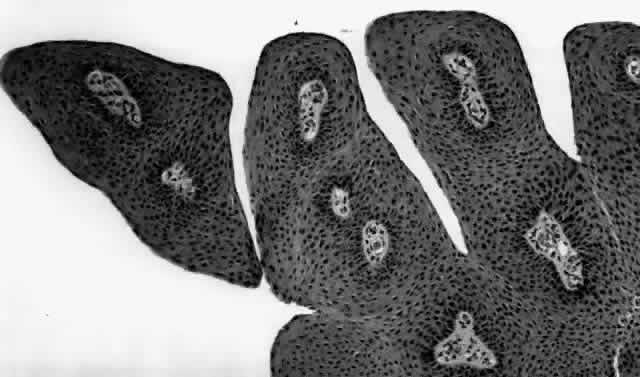

HPV-induced conjunctival squamous papillomas demonstrate papillomatosis, acanthosis, and koilocytosis (Fig. 6). Because they are mucous membrane lesions, those of the conjunctiva and lacrimal sac show no granular cell layer but will show keratinization if they are large or exposed (Fig. 7). In our experience the frequency of koilocytes is variable, even in lesions almost certain to be viral (Fig. 8). Scattered inflammatory cells may be present in the cores or epithelium. Virus can be detected immunohistochemically in the nuclei of the cells (Fig. 9).

Early dysplastic lesions (conjunctival intraepithelial neoplasia) show thickened epithelium with extension of basal-like cells beyond the basal layer, but cells continue to mature into flat squamous cells. Mitoses are also seen higher in the epithelium. As the degree of dysplasia worsens, the more superficial epithelium is replaced at higher levels by basal-type cells, mitoses can be seen further from the basal layer, and atypia of cells becomes more pronounced. With squamous cell carcinoma in situ, there is full-thickness dysplasia, cellular atypia is variable, and mitoses can be seen at all layers of the epithelium. Invasive squamous cell carcinomas are usually well differentiated. Pleomorphism, hyperchromaticity, dyskeratosis, and horn pearls are seen. Epithelial cell clusters can be seen invading below the basement membrane. Inflammatory cells are common in the substantia propria.

Squamous papillomas of the eyelid are exophytic lesions with multiple fronds, each showing acanthotic epithelium around a fibrovascular core. There is typically hyperkeratosis and koilocytosis. Inflammatory cells may be present.